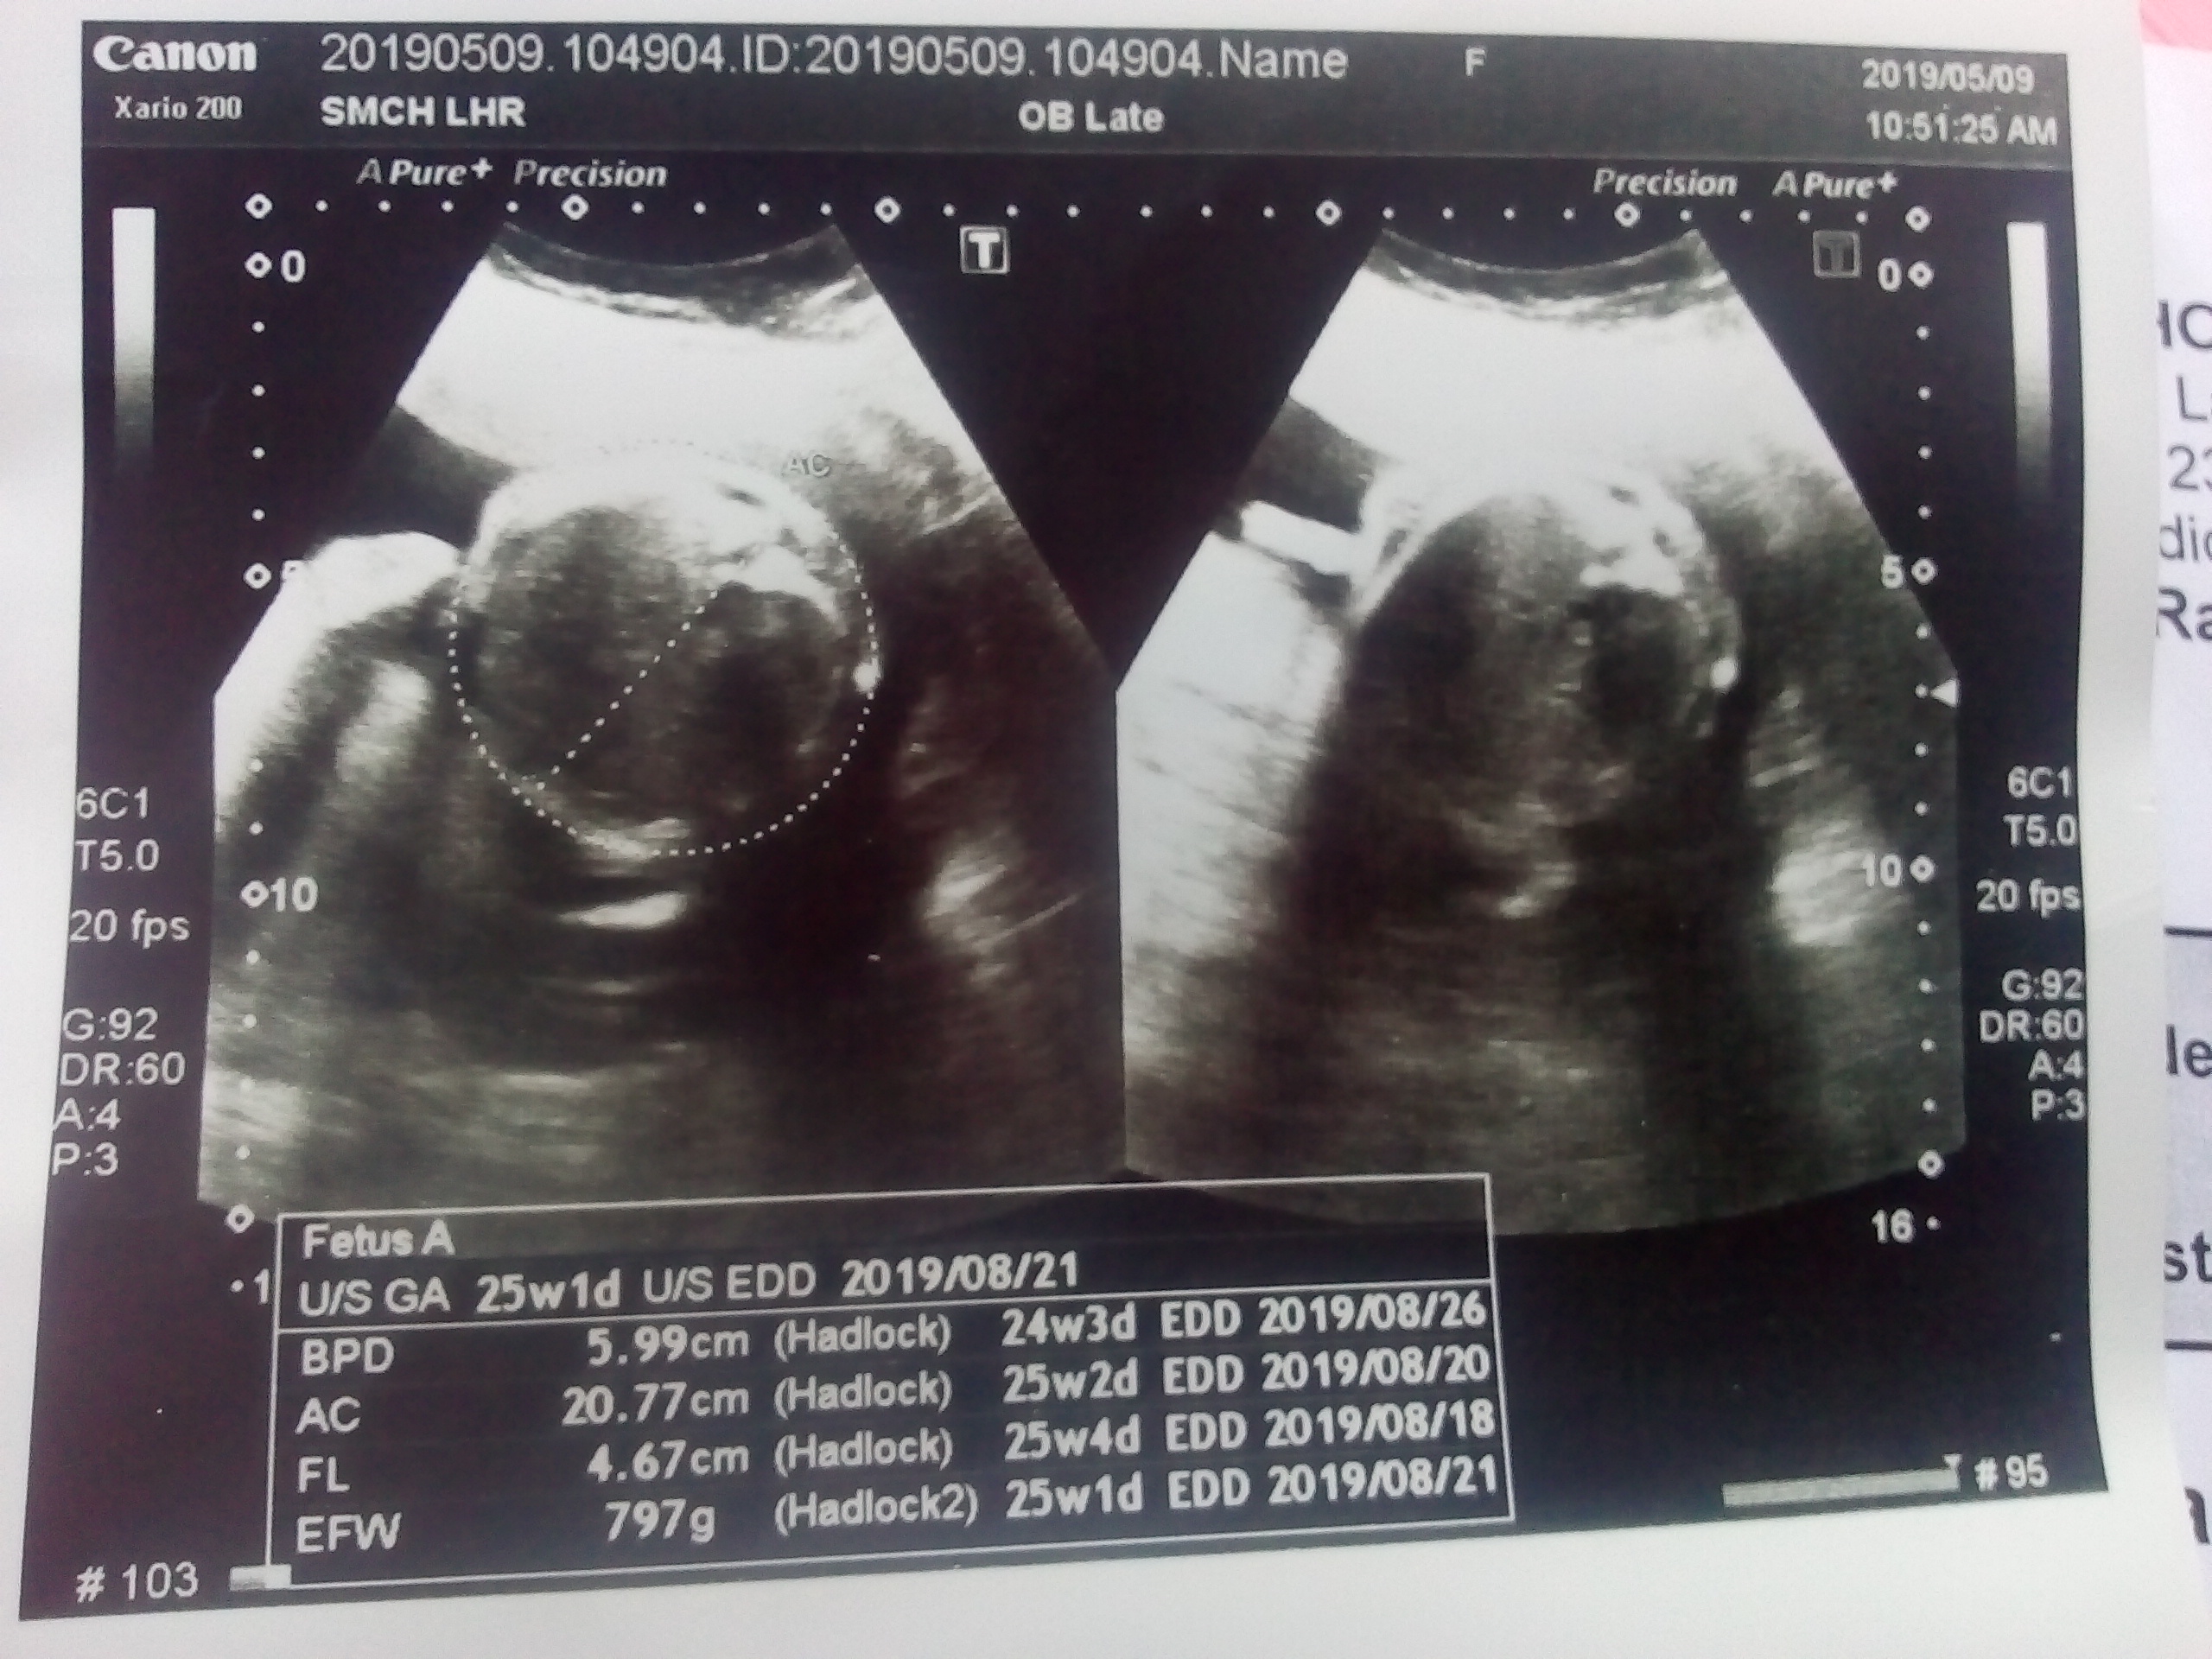

aslam o alikum, meri 25 weeks pregnancy ki altrasound pics Gender bta sakty hen altra sound pics dekh k please....... jazakAllah

Thank you for your mail. it is not possible on pics to tell you the gender.. This requires real time imaging.

Ws.. Unfortunately its not possible to comment about gender on still/static images. You can ask your radiologist while he/she is performing the ultrasound for your gender related queries. I hope that helps :)

Not possible with the provided images ?